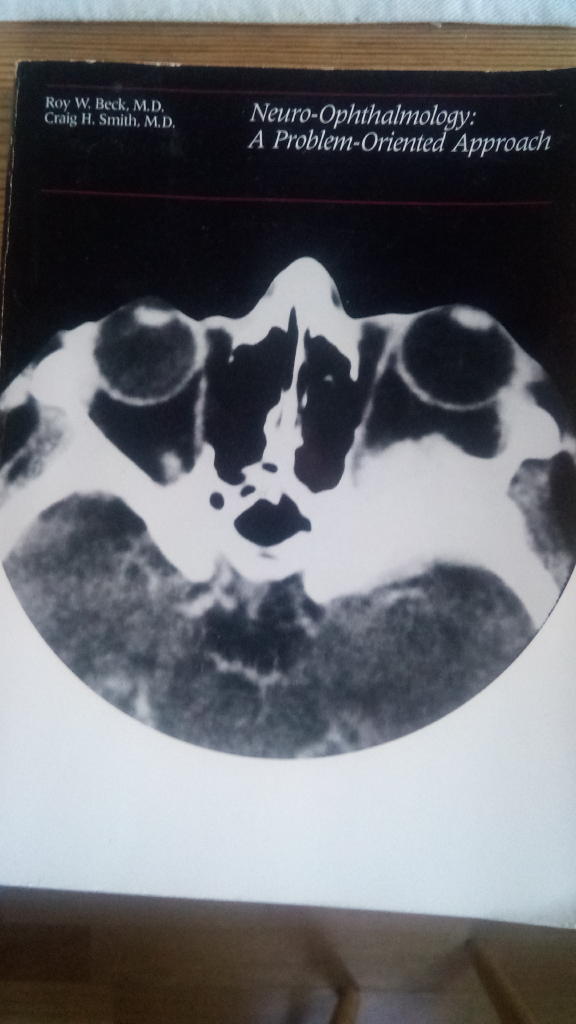

Neuro-Ophthalmology. A problem-oriented appro...

Häftad bok. Little, Brown and Company. First edition. Second printing uppl. 1988. 364 sidor.

Gott skick. Namnad, en hel del understrykningar i texten.

Illustrerad med foto och teckningar.

Inrikes enhetsfrakt Sverige: 62 SEK- ISBN

- 9780316086516

- Titel

- Neuro-ophthalmology : a problem-oriented approach

- Författare

- Beck, Roy W - Smith, Craig H

- Utgivningsår

- 2019

- Språk

- English

Little, Brown and Company First edition. Second printing 9780316086516 -